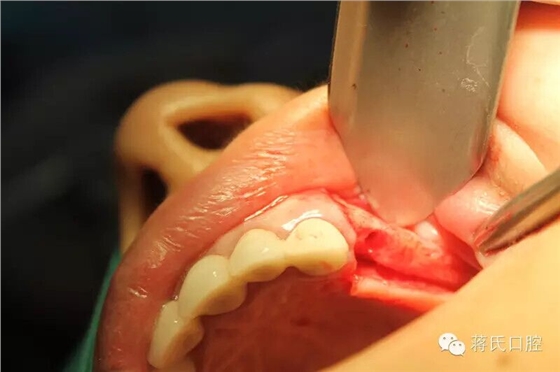

10.左側(cè)切開(kāi)后

12.左側(cè)外提升過(guò)程